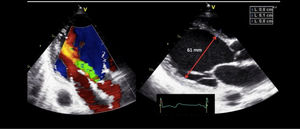

Valoración del volumen sistólico (fig. 2)Se puede realizar por medio de la integral velocidad-tiempo (IVT) y el diámetro del tracto de salida del ventrículo izquierdo (TSVI).

Estimación del volumen sistólico (VS) y del gasto cardiaco (CO) a través de la integral de velocidad (VTI) y radio (r) del tracto de salida del ventrículo izquierdo (TSVI). A) Paraesternal izquierdo ventrículo izquierdo en sístole. B) Zoom TSVI. C) Doppler pulsado TSVI 5C apical. D) Cálculos.

Un IVTTSVI<11cm se correlaciona con un índice cardiaco <2 l/min17,18.